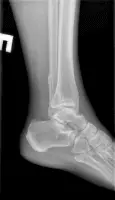

Стандартний рентгенографічний аналіз області гомілковостопного суглоба включає візуалізацію 2 видів: прямого заднього та бокового. У деяких випадках роблять знімок у косій проекції.

Прямий задній вигляд дозволяє оцінити стан суглобової щілини, яка має ширину 3-4 мм. Також на знімку можна розглянути кісточку, таранну та гомілкові кістки. Щоб досліджувати їх детальніше, використовується коса проекція.

Бічний вигляд дозволяє виявити переломи, вивихи та суглобові випоти навколо гомілкостопа. Крім того, проекція допомагає в оцінці тяжкості травм кістки п’яти шляхом вимірювання кутів Беллера і Гиссана, які в нормі рівні 20-40° і 94-136° відповідно.

При розгляді рентгенограм вивчаються м’які тканини на наявність набряку. Скупчення рідини в області зчленування латеральної та медіальної кісточок є ознакою переломів та травм зв’язок. Випіт може бути ідентифікований за наявності ущільнень тканин спереду та ззаду суглоба.

На знімках погано видно зв’язки та сухожилля, проте добре проглядається ахілове сухожилля. Його нормальний діаметр у середньому становить 6 мм. Значення параметра понад 8 мм вказує на патологію сухожиль, причиною може бути дистрофічне ураження найближчих м’язів, розрив, запальні артропатії, післяопераційні зміни.